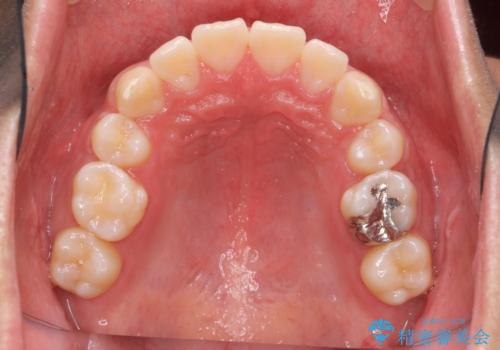

矯正後8年目になりますが、並びも綺麗に保持でき、また上下の歯がさらにしっかり咬んできているのがわかります。

下は歯につけるタイプのワイヤーを貼っています。

上は取り外し式の装置を就寝時使っていただいています。

さしたる問題もなく、半年~1年に一度のメインテナンスにお越しになっている患者様です。保定装置については、慣れれば習慣化するためさほど負担ではありません。

矯正をしなくても起こる下の前歯のがたつきも予防でき、若々しい歯並びを維持することができます。